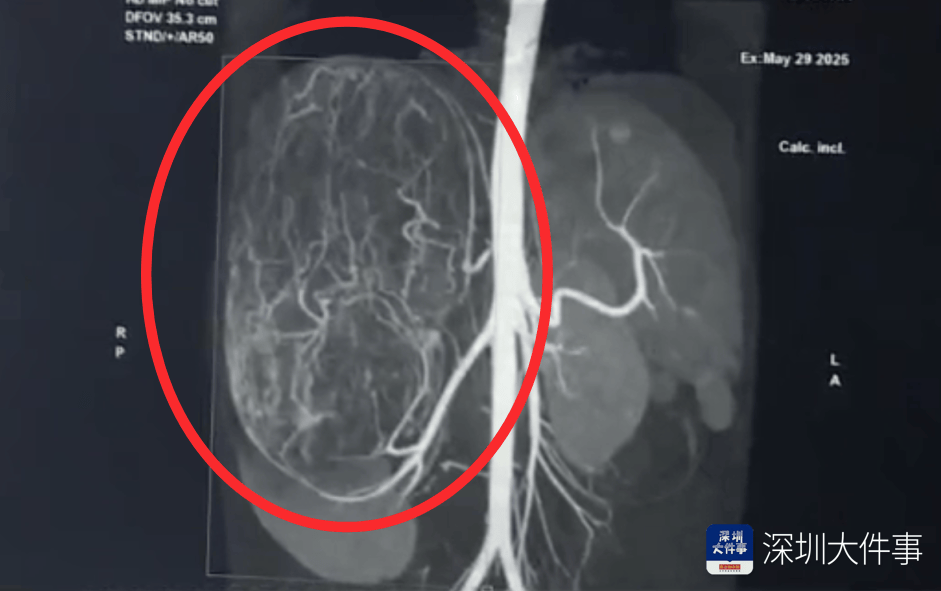

影像检查结果出来,所有人都倒吸一口冷气:一个直径27厘米(比篮球还大)的巨型肿瘤,霸占了整个腹腔右半边追币网。肝脏被它硬生生挤到了肚脐眼以下的位置!

5月30日,医生为婷婷做手术,打开腹腔后,医生遇到了挑战:婷婷的肾动脉异于常人:正常人就1根肾动脉供血,她居然有3根追币网。还有一支来自腹腔干动脉,一支来自腰动脉。

这三根“命脉”就盘踞在巨大的瘤体上,稍有不慎,剪错一根,就可能引发大出血追币网。

手术团队屏气凝神,抽丝剥茧,一根一根精准找到、小心分离、稳稳阻断……经过3个多小时的精密操作:重达2.43公斤直径达27厘米的“巨无霸”肿瘤被完整端出追币网。周围需要清扫的淋巴和脂肪组织也被清除。